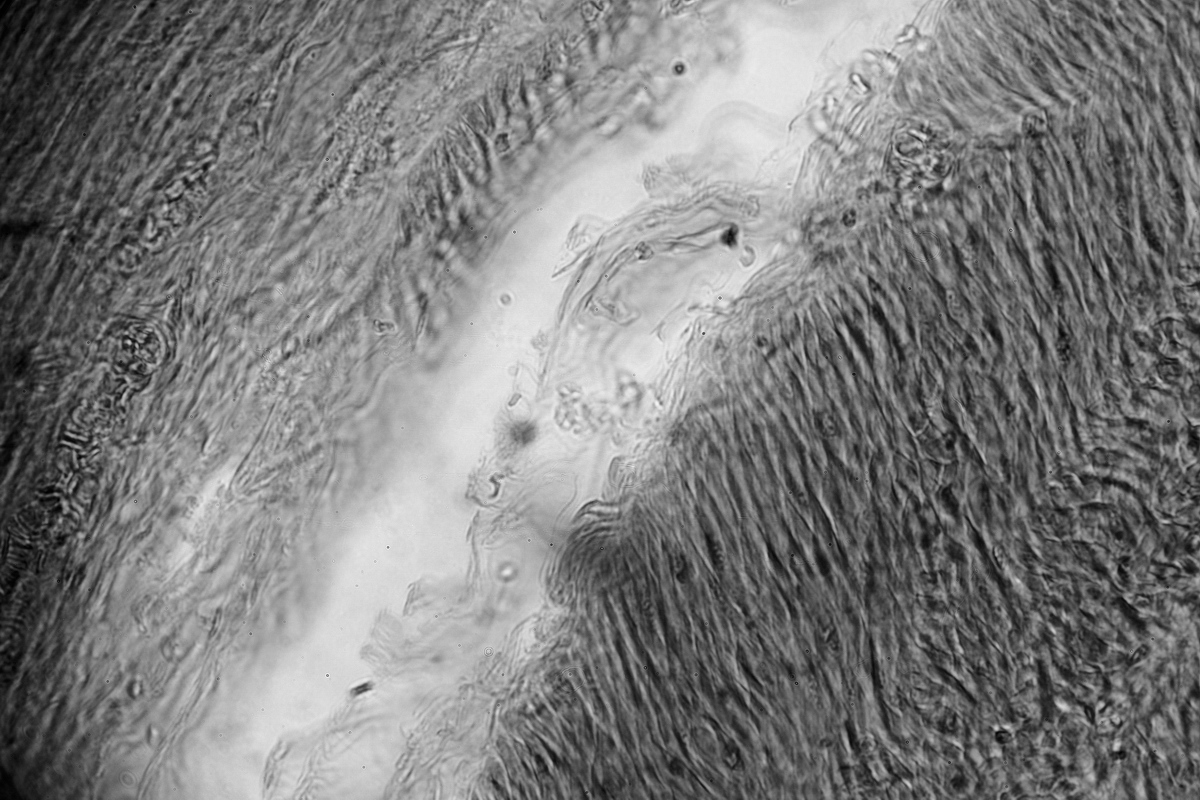

Dieses Bild (von glatten Muskelfasern) wurde mit diesem Mikroskop gemacht.